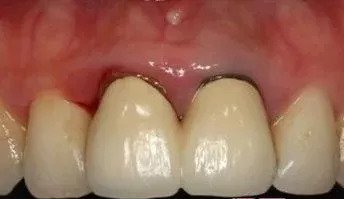

图片

烤瓷冠的牙龈黑线问题